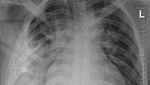

Jakarta - Begini penampakan pisau yang menancap di dada seorang pria di Tanzania. Pasien baru menyadari di tubuhnya ada pisau 8 tahun kemudian.

Foto-foto Penampakan Pisau Menancap di Dada, Pasien Sadar Setelah 8 Tahun